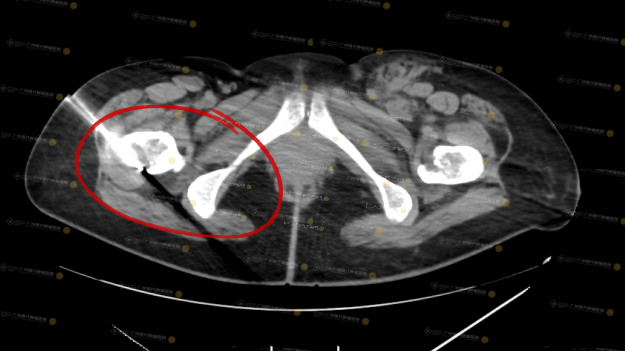

Trong đó, một trường hợp bệnh nhân ung thư vú kèm di căn xương có điểm đau (NRS) lên tới 10 trước điều trị, dù đã sử dụng liều cao thuốc giảm đau thông thường nhưng hiệu quả vẫn kém. Sau khi được hội chẩn MDT, bệnh nhân được chỉ định đốt lạnh khối u dưới hướng dẫn CT. Sau điều trị, mức độ đau giảm rõ rệt, đồng thời chất lượng cuộc sống được cải thiện đáng kể.

được chỉ định thực hiện cấy hạt phóng xạ

Điểm NRS sau điều trị